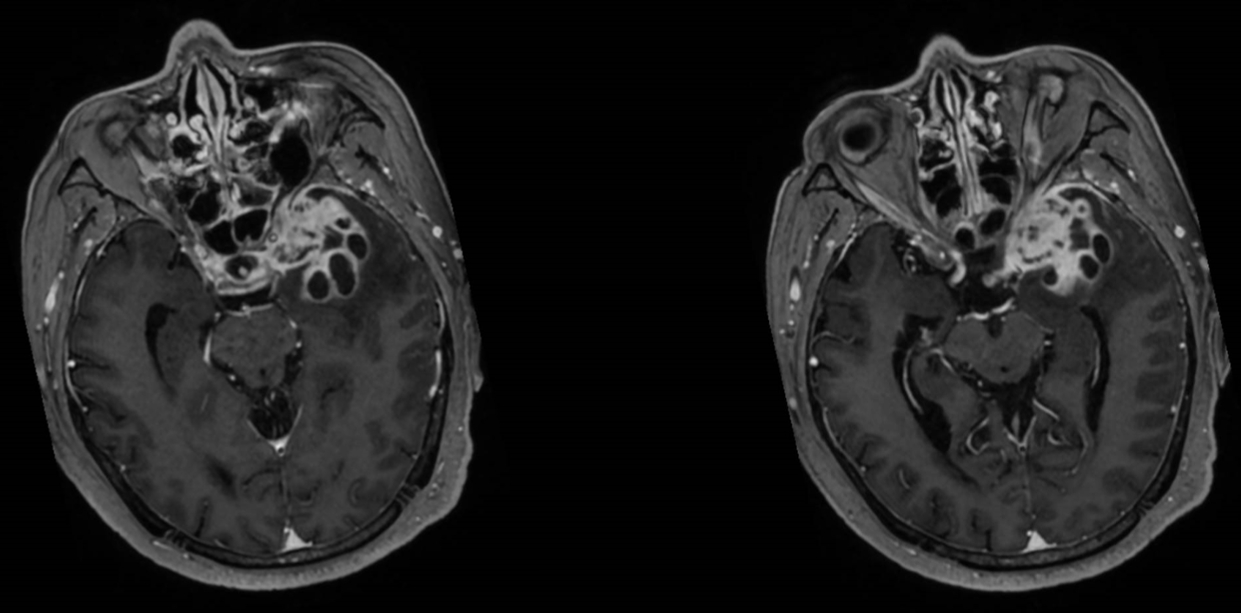

该患者入院后完善常规颅脑影像学检查,左侧颞叶病变,疾病性质不详,转移瘤、胶质瘤、炎症类疾病均不能排除,遂行PET-CT检查,提示左侧颞叶高代谢,淋巴瘤不能排除。组织MDT会诊建议可先行腰椎穿刺查脑脊液脱落细胞学、感染指标,若仍不能确诊,可进一步行开颅病灶切除,术中快速冰冻,根据冰冻结果决定手术手术策略。患者脑脊液脱落细胞学结果:较多淋巴细胞,少许单核细胞及个别中性粒细胞,未见异形细胞,脑脊液常规、生化、脑脊液培养未见细菌生长,诊断仍不能明确,且患者病情进展迅速,患者神志呈昏睡状态,颅脑MRI提示病变较前明显增大(影像学检查间隔两周),且水肿明显加重,遂行开颅病变切除术。术中见部分病变累及蝶骨嵴硬膜,病变质地硬韧,内有多个囊腔,囊内容物为黄色粘稠样脓性物质,留取囊液及实性部分送快速冰冻,在等待冰冻过程中,进一步探查见肿瘤侵犯左侧颞叶,该部位肿瘤质地相对软,无包膜,与周围脑组织无边界,血运不丰富,内有多个囊腔,且肿瘤侵犯侧裂池、颈动脉池,左侧视神经、颈内动脉、大脑中动脉均被病变包绕,且该处肿瘤质地偏硬韧。术中快速冰冻提示组织大片变性坏死,伴胶质增生及淋巴增生。结合病变质地及冰冻结果,考虑为非肿瘤性疾病,可能为炎性病变伴肉芽肿形成可能性大,且肿瘤质地硬韧,累及范围广泛,难以全切,遂行肿瘤大部分切除后结束手术。术后病理结果明确后予以伏立康唑、醋酸卡泊芬净抗真菌治疗。在治疗过程中患者先后出现脑出血、脑梗塞,最终因治疗周期长,花费高、效果不确定等因素,家属放弃治疗,于术后1月去世。